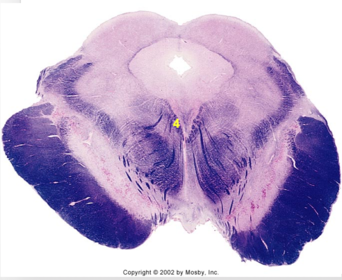

| Nucleus gracilis | |

| Accessory nucleus | |

| Medial longitudinal faciculus | |

| Pyramidal decussation | |

| Medullary pyramids | |

| Anterior spinocerebellar tract | |

| ALS | |

| Posterior spinocerebellar tract | |

| Spinal tract of V | |

| Spinal nucleus of V | |

| Nucleus cuneatus | |

| Fasciculus cuneatus | |

| Fasciculus gracilis | |

| Central canal | |

| Internal acruate fibers | |

| Lateral (external/accessory) cuneate nucleus | |